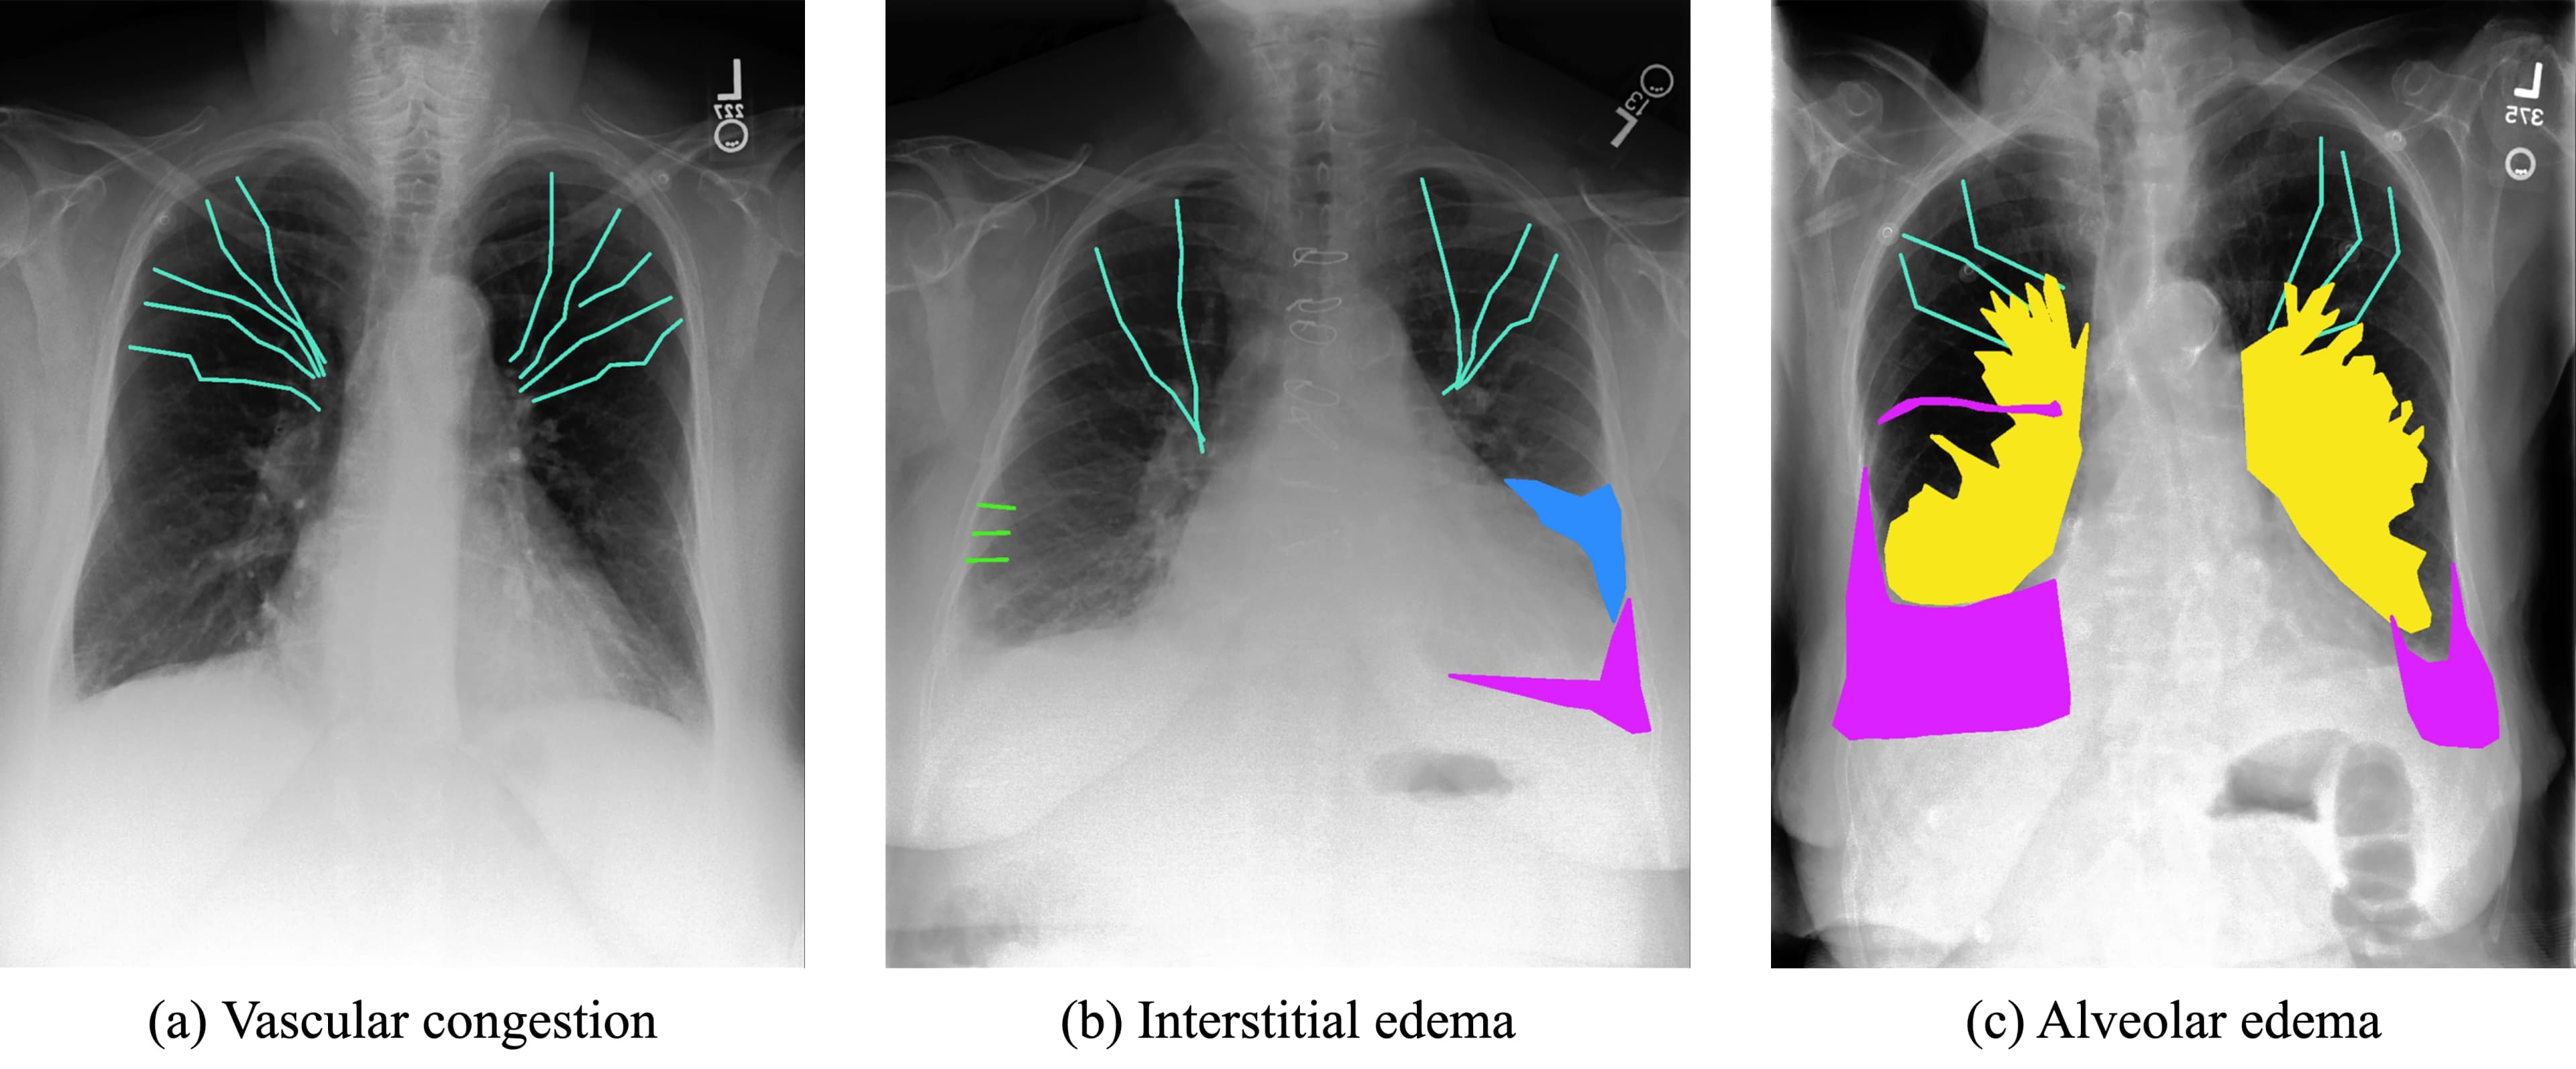

- •Annotation Method: Cephalization and Kerley lines were delineated using polylines; pleural effusion, bat wings, and infiltrates were marked with binary segmentation masks.

Radiological features such as cephalization, Kerley lines, pleural effusion, bat wings, and infiltrates were labeled by an experienced radiologist (Figure 1).